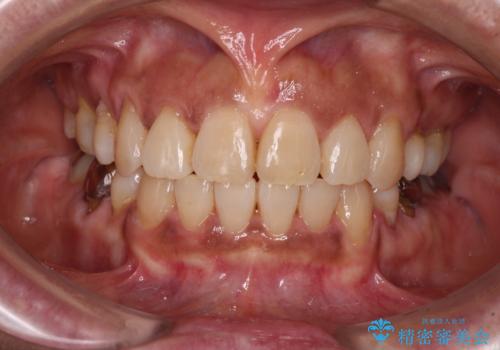

[ 再生治療・歯周外科・小矯正・セラミック補綴 ] 前歯の歯周病治療

担当医 大元洋佑

![[ 再生治療・歯周外科・小矯正・セラミック補綴 ] 前歯の歯周病治療の症例 治療前](https://seimitsushinbi.jp/wp/wp-content/uploads/2022/12/83065c2454a29ed71cf190e15a6106f4-500x350.jpg?v=1671673398)

![[ 再生治療・歯周外科・小矯正・セラミック補綴 ] 前歯の歯周病治療の症例 治療後](https://seimitsushinbi.jp/wp/wp-content/uploads/2022/12/ec16e37ee53325a6f6629b94759f5513-500x350.jpg?v=1671673454)